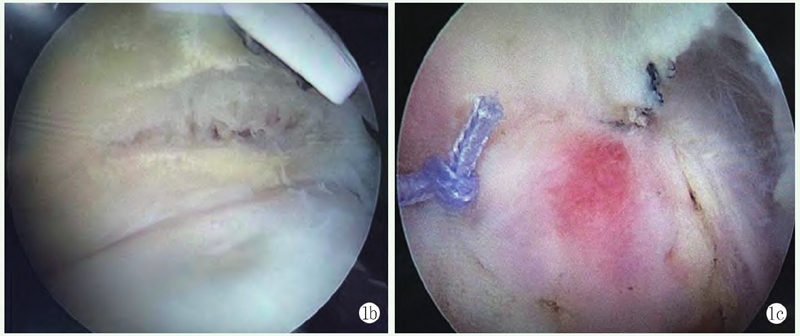

影像学检查:X线片显示左肱骨头解剖颈处小骨片(图1a),彩超示:左肱骨头解剖颈处小撕脱骨片。

1a:术前肩关节正位 X 线片示左肱骨头解剖颈处小骨片

手术:采用全麻联合臂丛神经阻滞麻醉。右侧卧位左肩外展牵引下手术。左肩关节后方及前方建立关节镜手术入路,关节镜探查盂肱关节见盂唇附着完好,肱骨头关节面边缘冈上肌附着处可见全层软骨及软骨下骨撕脱骨折片5~6mm,冈上肌从肩关节撕裂(图1b)。置入带线锚钉通过Trans-Tendon法用腰穿针将锚钉尾端缝线穿过冈上肌后打结固定骨折块(图1c)。

图1b: 镜下见冈上肌关节面横行撕裂;1c: 置入锚钉,用腰穿针将锚钉尾端缝线穿过冈上肌后打结固定骨折块